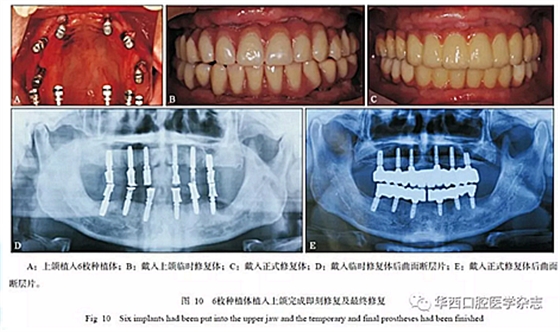

本病例最小唇側(cè)基托邊緣位于前牙區(qū)牙槽嵴的冠方,前牙區(qū)牙槽嵴寬度可以支撐口唇凸度,但齦緣位置距離牙槽嵴頂距離大于4 mm,不是單純的牙缺失,為MLTR-Ⅰ類2亞類;與患者討論后決定采用復(fù)合式義齒修復(fù)。 采用微創(chuàng)技術(shù)進(jìn)行上下頜種植手術(shù)(圖10A),放置多基基臺(tái),制作臨時(shí)修復(fù)體(圖10B、D),待3個(gè)月種植體骨結(jié)合完成后,完成最終修復(fù)(圖10C、E和圖11)。